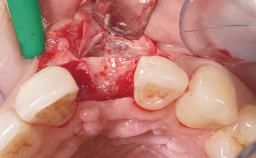

A 29-year-old female patient presented for treatment to replace the upper left central incisor tooth with an implant- supported restoration. The tooth had been intermittently symptomatic for the previous 12 months. The tooth had originally suffered trauma about 15 years previously. Several endodontic treatments had been performed, including an apicectomy procedure to retain the tooth. The patient was healthy and a non-smoker. She had reasonable expectations in regard to esthetic outcomes and the risk of marginal tissue recession following treatment. At medium smile, the gingival margins of the upper teeth were visible, with a display of 3 to 4 mm of the gingival margins. Gingival recession of tooth 21 and a discrepancy in the gingival levels between teeth 11 and 21 was observable during normal speech and smile.

Placement Protocol Immediate implant placement

Tooth Site Maxillary incisor or canine

Socket Morphology Single-root socket

Socket Integrity Damage to one or more bone walls

Bone Volume Damage to one or more socket walls